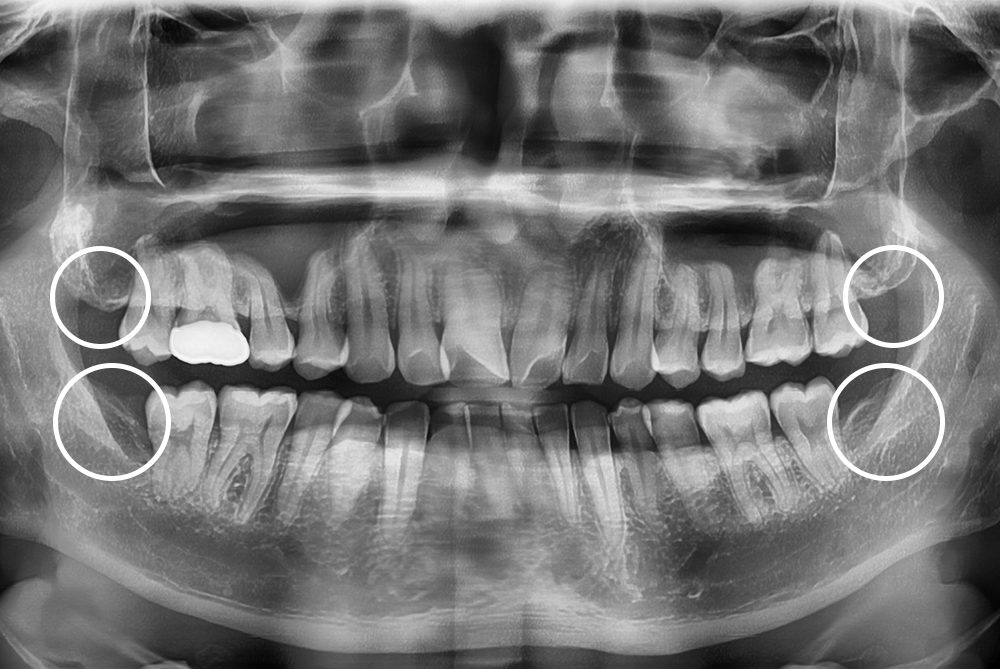

[사랑니] 매복 사랑니 발치

치료후 : 2022-01-08

세종치과는 구강악안면외과학 박사이신 원장님이 발치하는 치과입니다.